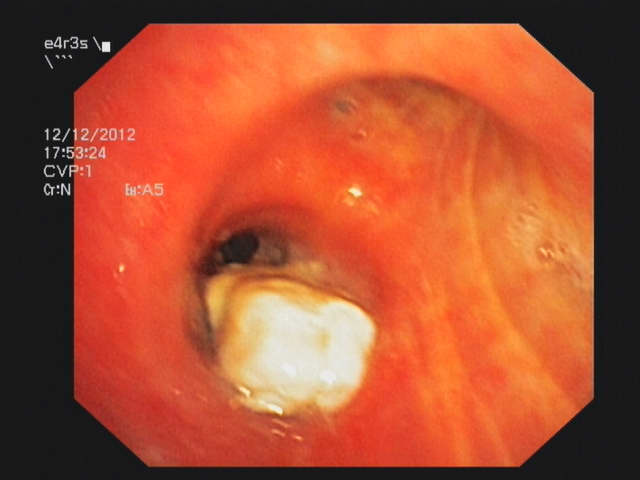

Endobronchial lymphoma of the truncus intermedius

Endobronchial lymphoma with necrotic tissue causing an obstruction of the truncus intermedius.